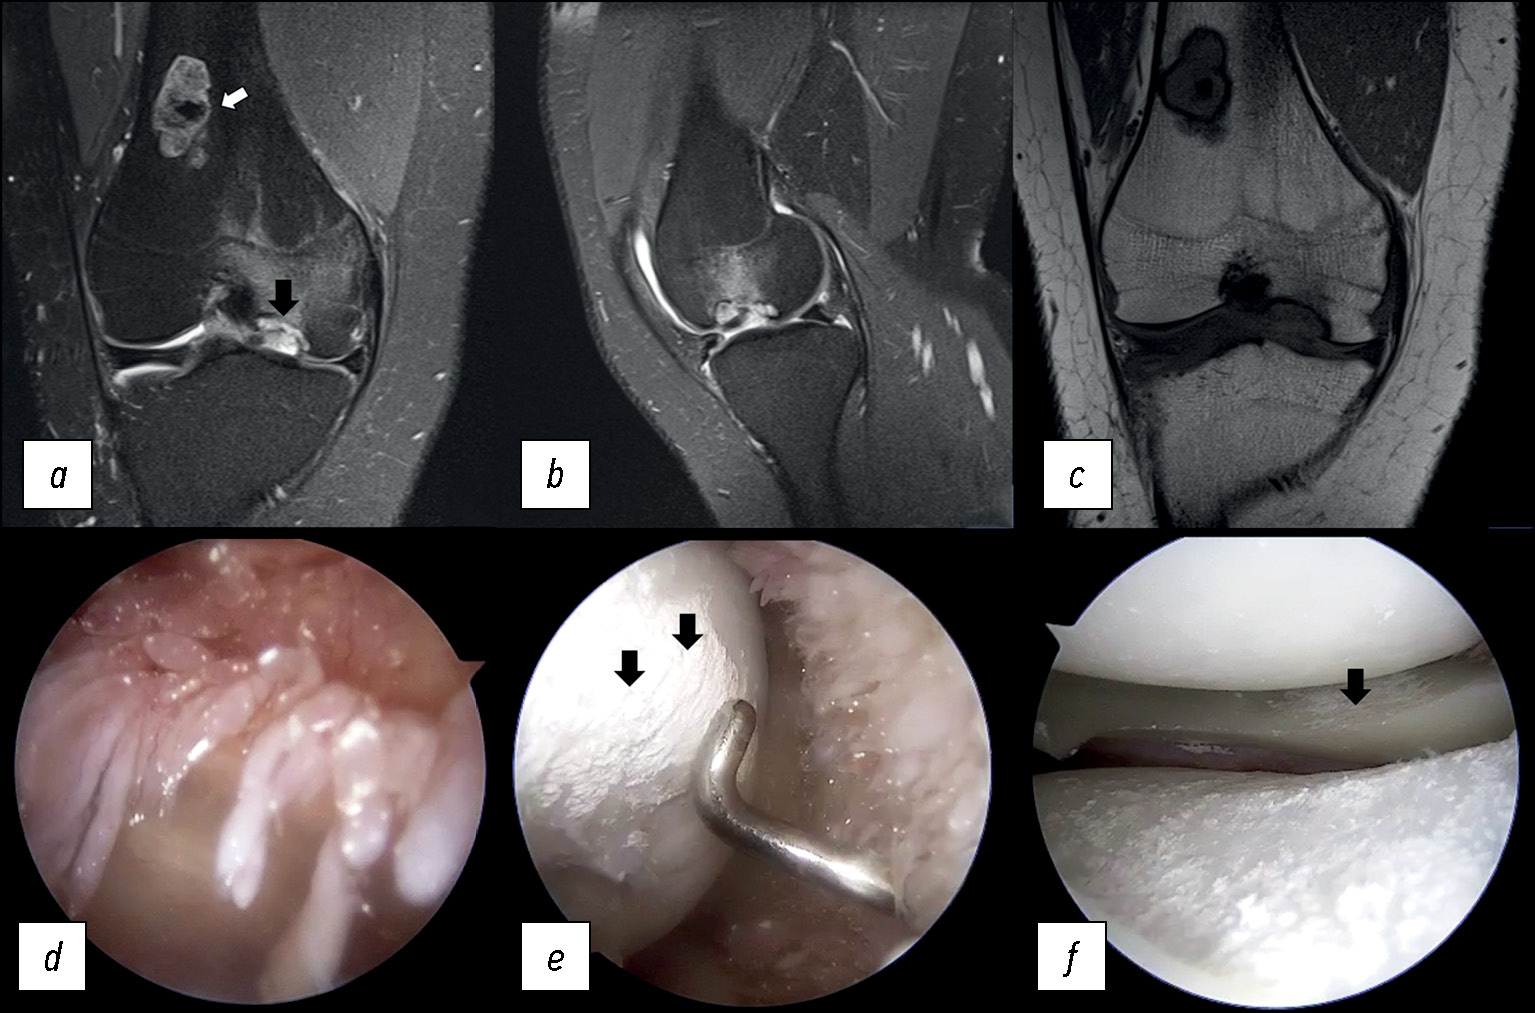

Пациент К., 21 год, в течение нескольких месяцев отмечает боль в области коленного сустава, периодически — блокады правого коленного сустава с ограничением сгибания и разгибания. Проводился дифференциальный диагноз между рассекающим остеохондритом коленного сустава, травматическим повреждением с развитием свободного внутрисуставного тела и метаболической артропатией.

Отёк костного мозга, выявленный на МРТ (рис. 9), распространялся на весь внутренний мыщелок бедренной кости, сочетался с развитием костно-хрящевого дефекта и наличием свободного внутрисуставного тела.

Рис. 9. МР-томограммы коленного сустава при болезни депонирования кристаллов пирофосфата кальция: a, b — корональная и сагиттальная проекции в режиме PD FS с подавлением сигнала от жировой ткани, c — корональная проекция в режиме Т1 (белая стрелка — энхондрома бедренной кости, чёрная стрелка — область остеохондрального дефекта), d, e, f — артроскопическая картина (чёрные стрелки — области отложения кристаллов пирофосфата кальция на гиалиновом хряще мыщелка бедренной кости и на поверхности мениска) при пирофосфатной артропатии коленного сустава.

Fig. 9. MRI scans of the knee: a, b — coronal and sagittal views in to suppress the signal from adipose tissue with a pyrophosphate arthropathy, c — coronal views in to T1 (white arrow — enchondroma of the femur, black arrow — area of osteochondral defect), d, e, f — arthroscopic views (black arrows — areas of deposition of calcium pyrophosphate crystals on the hyaline cartilage of the femoral condyle and on the surface of the meniscus) with pyrophosphate arthropathy of the knee joint.

Во время артроскопии коленного сустава на поверхности гиалинового хряща отмечено отложение кристаллов, что подтверждало болезнь депонирования кристаллов пирофосфата кальция.